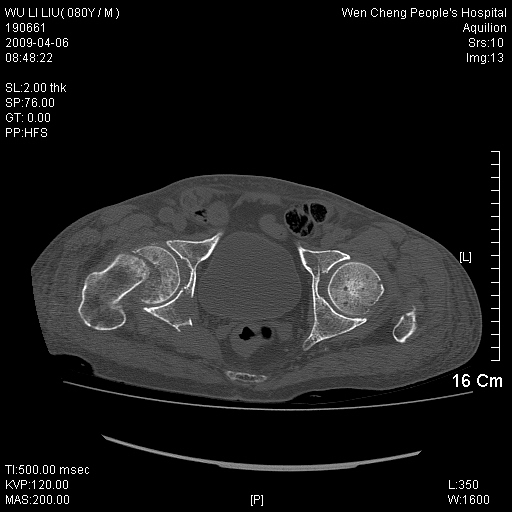

以下是引用zjzjr在2009-4-7 12:13:00的发言:[br]支持多发性转移瘤,右股骨颈骨折,腰椎亦有压缩性骨折.肝内胆管结石伴胆内外胆管扩张,左肾结石.

以下是引用liaoqiang在2009-4-7 8:44:00的发言:[br]考虑多发性骨髓瘤伴肝肺转移、肝内胆管结石、左肾结石、右股骨颈骨折。

以下是引用余辉在2009-4-7 8:52:00的发言:[br]椎骨及骨盆骨质疏松,骨破坏主要累及椎体,各骨破坏较广泛,各病灶边缘均较清晰锐利,血沉增快,白细胞增高.支持考虑多发骨髓瘤,建议查本尿周氏蛋白.[br]胆内胆管及左肾结石[br]右股骨颈骨折,考虑病理性